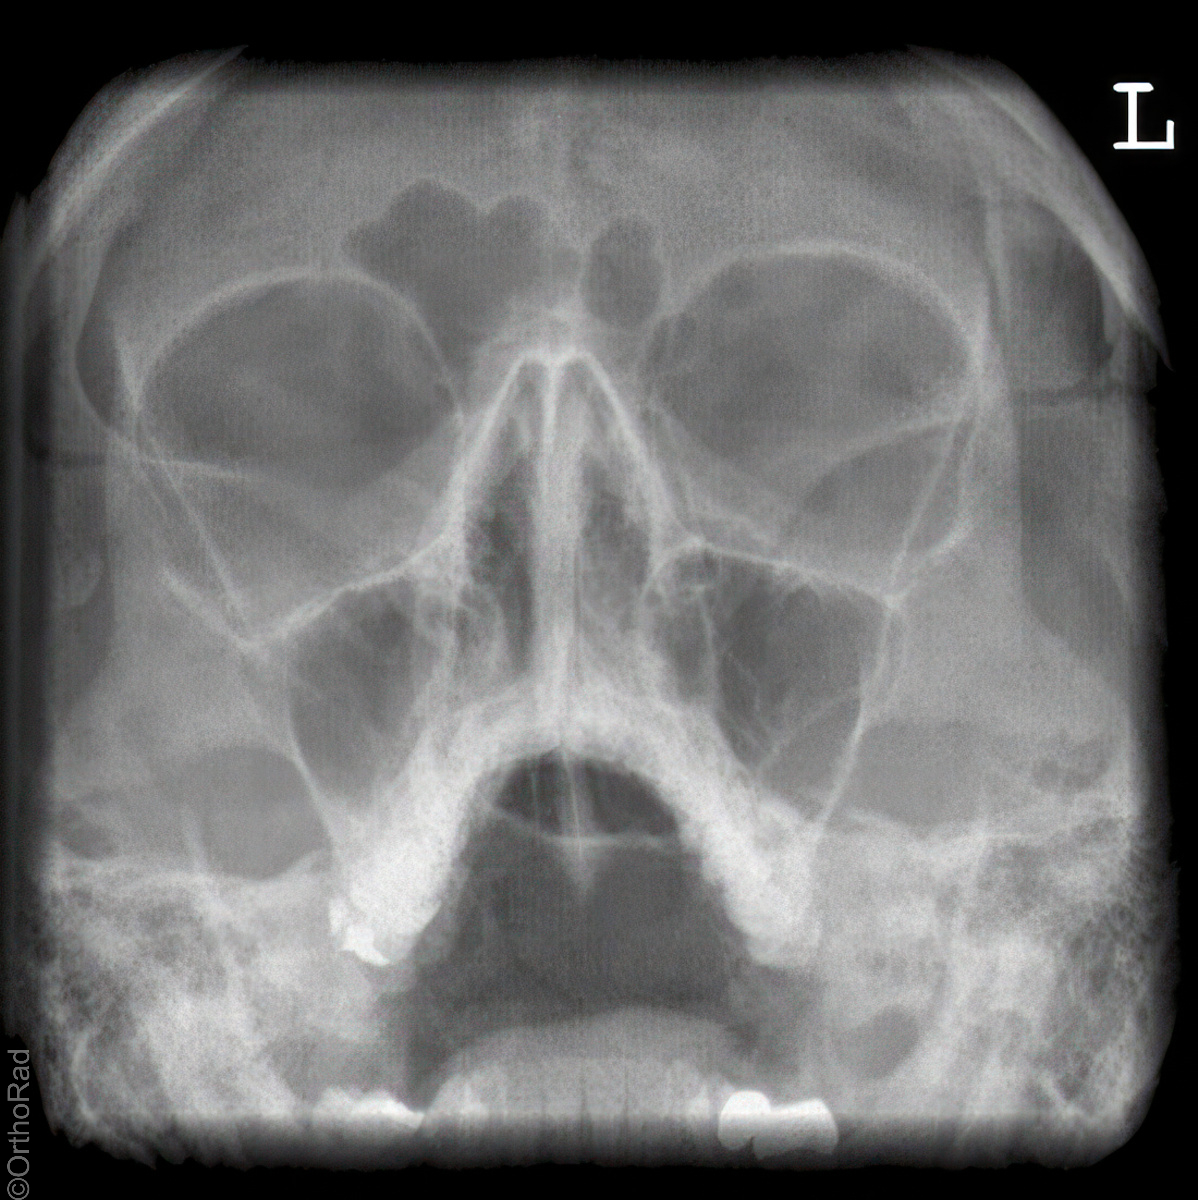

Nasennebenhöhlen (NNH)

Es wurden keine Bilder gefunden.

Indikation

Sinusitis, Z. n. Osteosynthese

Qualitätskriterien

Symmetrische Darstellung des Gesichtsschädels: seitengleiche Distanz zwischen lateralem Rand der Augenhöhle und äußerer Schädelkontur. Die Pyramidenoberkanten kommen unmittelbar unterhalb des Kieferhöhlenbodens zum Liegen, also in die obere Zahnreihe, sodass die Kieferhöhlen überlagerungsfrei zur Darstellung kommen.